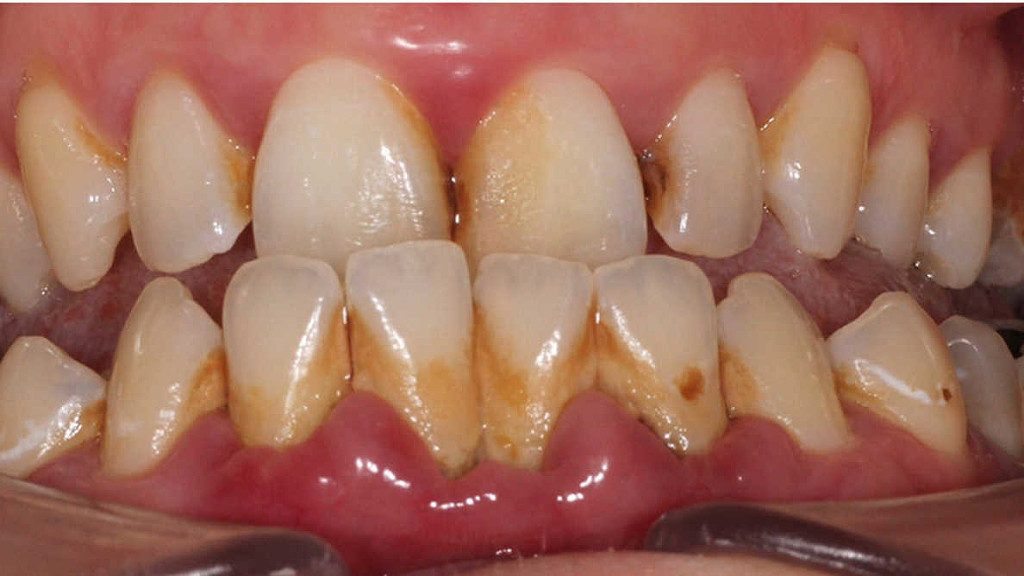

Oral biofilms, a concern for all dental professionals

Biofilms are a collective of one or more types of microorganisms that can grow on many different surfaces. Microorganisms that form biofilms include bacteria, fungi and protists.

One common example of a biofilm dental plaque, a slimy buildup of bacteria that forms on the surfaces of teeth. Pond scum is another example. Biofilms have been found growing on minerals and metals. They have been found underwater, underground and above the ground. They can grow on plant tissues and animal tissues, and on implanted medical devices such as catheters and pacemakers.

Role of oral biofilm in the aetiology of disease:

Oral biofilm is medically important because it has broad implications for maintaining not only oral health but also systemic health. It is estimated that biofilms account for over 80% of microbial infections in the body. Research has undoubtedly shown that biofilm-dependent infections, including oral diseases such as caries, and periodontal and endodontic disease, thus pose major public health and cost concerns globally.

Periodontal disease, in particular, is considered one of the most prevalent diseases worldwide, affecting up to 50% of the world’s adult population, according to FDI World Dental Federation. Previous research has established connections between periodontal disease and preterm births, low birthweight, diabetes, and risk factors associated with cardiovascular disease and stroke. Globally, periodontitis is responsible for an estimated US$54 billion per year in lost productivity and a major portion of the US$442 billion spent annually on oral disease, according to the European Federation of Periodontology.

Control of oral biofilm:

Owing to the vast implications of oral biofilm for dental and general health, its effective control represents a major challenge. There is no question that the formation and maturation of oral biofilm need to be tackled by dental professionals across all specialties in all countries worldwide.

“The backbone of any therapeutic and preventive approach is the disruption of the intra-oral biofilm. An example of technologies that have been successfully demonstrated to aid supra- and subgingival instrumentation are air polishing devices with low-abrasive powders that can disrupt the biofilm on all intra-oral surfaces, including mucous membranes and difficult-to-reach subgingival areas, without harming the hard tissue and the even more vulnerable soft tissue,” Beikler explained. “Their effects can be augmented by antimicrobial and immune- and microbiome-modulating strategies. Regarding the latter, probiotics offer an interesting and promising alternative to the use of unspecific antimicrobial agents like chlorhexidine or phenolic compounds. However, additional research, that is, appropriately designed and well-structured multicentre clinical trials, is critically needed to fully appraise their therapeutic effects,” he continued.

Another major challenge that needs to be taken into consideration in this respect is that trying to eliminate a specific pathogen using antimicrobial agents may disturb the sensitive microbial ecology and eventually induce microbial dysbiosis of the oral cavity.

Education on oral biofilm:

Until the early 1990s, dentists confined their treatment for combating oral plaque to removing calculus twice a year because there was only limited understanding of biofilm. Over the past decades, research on and improved knowledge about the parameters that determine the development of oral disease have spurred the development of new preventive strategies. For instance, piezoceramic instruments and low-abrasion powders have made professional biofilm management safer, minimally invasive and more comfortable for both the patient and the dental practitioner. Moreover, the launch and further development of AIRFLOW devices by EMS fundamentally changed biofilm management and eventually resulted in the development of Guided Biofilm Therapy, an innovative concept for contemporary prophylaxis.

As research and development of new technologies and therapies continues to progress, so too does knowledge in the dental professional community need to advance for effective integration of these developments into everyday practice for the well-being of the patient.

“As biofilms can be found on all oral surfaces, it is clear that all dental disciplines, ranging from dental hygienists to orthodontists, are highly affected by oral biofilm and its sequelae,” highlighted Beikler. “Unfortunately, prevention is sometimes still considered to be toothbrushing augmented by some kind of professional tooth cleaning. However, the whole oral cavity should be the therapeutic focus of a systematic preventive approach.”